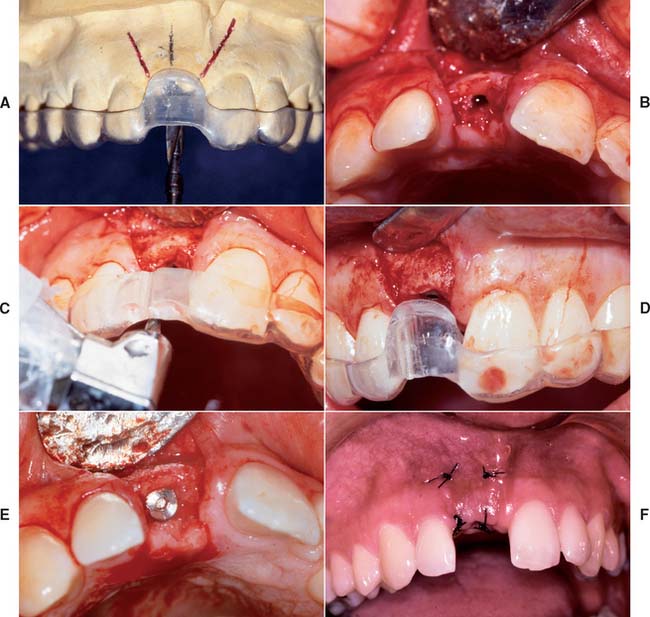

Fig. 13-20 Anterior implant placement with a surgical guide template. A, The apical extent of the template is not removed, which allows the superoinferior orientation of implant placement to be determined. B, Full-thickness flap incisions are made, preserving the interdental papilla. The flap is reflected to expose bone for preparation of the implant site. C, Resin (2.0 mm) has been added to the lingual aspect of the matrix; the rest of the lingual area was left open so the surgeon can choose the best available bone. The site should be prepared as close to the template as possible. D, The implant is positioned 2.5 to 3.0 mm apical to the desired emergence position of the final restoration. E, The implant is positioned at an angle and depth that allows optimum esthetics and access for hygiene. F, The surgical site is sutured. A 4 to 6-month healing time is allowed.

(Courtesy of Dr. J. A. Holloway.)

The coordination of surgical and prosthetic procedures through proper treatment planning is one of the more crucial factors in obtaining ideal esthetic results for the implant restoration. A surgical guide template is extremely useful for anterior implants because slight variations in angulation can significantly affect the appearance of the final restoration. Fabrication of the surgical guide template has become a requirement in patients in whom it is necessary to optimize fixed replacement and ensure correct emergence profiles. Surgical templates can also be beneficial in areas where esthetics is less important. The objectives for using a surgical template in partially edentulous patients are as follows: (1) delineate the embrasures, (2) locate the implant within the restoration contour, (3) align implants with the long axis of the completed restoration, and (4) identify the level of the cementoenamel junction or tooth emergence from the soft tissue.

A clear resin facial veneer template is recommended for anterior implant placement to allow the surgeon access to the osseous receptor site and an unimpeded view of the frontal and sagittal angulations as the site is being prepared. This type of template is fabricated from a diagnostic waxing or denture tooth arrangement on a mounted cast. The waxing is duplicated with alginate or polyvinyl siloxane and poured in quick-setting stone. Then 1.5-mm (0.060-inch)–thick of vacuum-formed matrix material is adapted to the replicated cast. For accurate orientation, the vacuum-formed matrix should be trimmed to extend over the full facial surface of the teeth being restored and about a third of the facial surface of the remaining dentition. This template is removed from the duplicate cast and returned to the original cast. A 2-mm thickness of autopolymerizing resin is added to the lingual surface to compensate for the space occupied by the porcelain on the implant restoration (Fig. 13-20). (The total thick-ness, including an additional millimeter from the vacuum-formed matrix, is about 3.0 mm.) To make surgical guides appear radiopaque, barium powder is often added to the resin during its fabrication (see Fig. 13-8). The surgeon must stay as close as possible to this guide during implant placement, which allows maximum flexibility in selecting an implant site without violating the facial surface or forcing screw access holes to be located inappropriately in the facial surface of the restoration. Following this guide enables the surgeon to place a fixture in the best location with minimum undesirable sagittal angulation. If a cement-retained restoration is desired, the orientation of the implant can be slightly more facial.